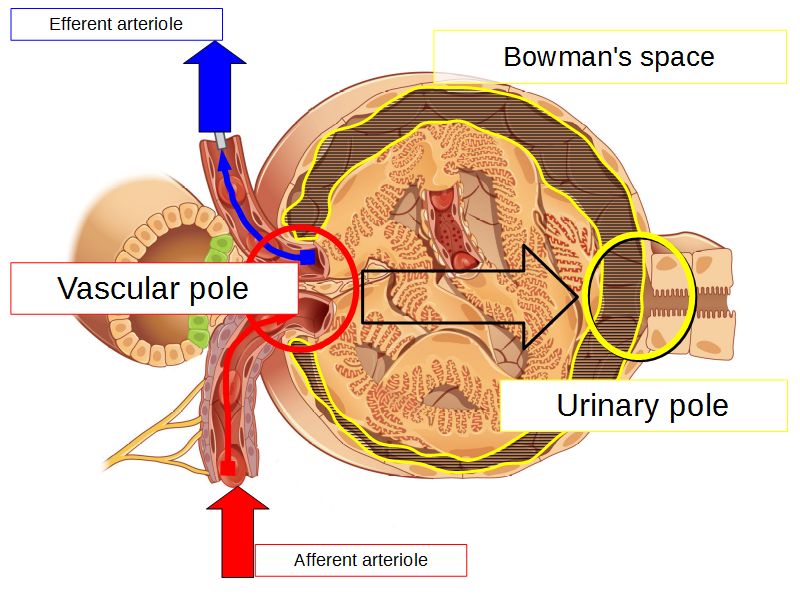

Renal corpuscle

- Tuft of capillaries

- grow into

- Blind end of nephron

- Several layers of epithelium

- Two sides

- Vascular pole

- Tubular pole

Blood flow

- Efferent arteriole

- Smooth muscle in media

- Capillaries

- Fenestrated

- Afferent arteriole

- Smooth muscle in media